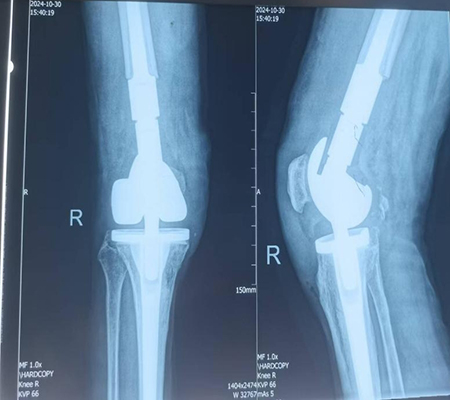

膝关节置换术后假体周围骨折特殊假体返修术后

手术由骨科专家许立新主任亲自主刀,在手麻科医护人员的全力配合下,顺利开展。手术过程中,发现膝关节假体彻底松动,胫骨假体也发生了松动,这再次证实了术前计划的合理性,去除松动假体后,安装特制肿瘤膝关节,手术过程非常顺利,仅用时86分钟。